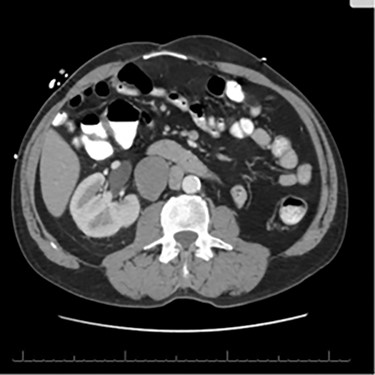

A 56-year-old male with a history of left testicular cancer treated with chemotherapy (Bleomycin, Etoposide, Cisplatin; BEP), radiotherapy, retroperitoneal lymph node dissection, and partial left nephrectomy in 1992 presented to hospital with complaints of left lower abdominal mass for 3–5 years, associated with ulceration and active drainage. He was asymptomatic with β-hCG and alpha-fetoprotein (AFP) levels within reference ranges (<2.39 and 1.4, respectively). On examination, inspection of abdomen revealed well-healed midline scar with bilateral incisional hernias and a 10 × 8 cm mass in the left lower quadrant (Fig. 1) firm and fixed to the abdominal wall. An open lesion characterized by yellow, non-purulent drainage was noted in the left lower quadrant. CT imaging of abdomen and pelvis with contrast revealed a multiloculated large cystic mass in the left inguinal canal measuring 11 × 7 × 7.7 cm (Fig. 2) along with a similar soft tissue nodule in the right inguinal area. A right retroperitoneal soft tissue mass in the mid abdomen was also identified, measuring 3.3 × 4.2 × 5.7 cm (Fig. 3). Changes of prior left nephrectomy and orchiectomy consistent with treatment of previous left-sided testicular cancer were also noted.

CT scan axial cut evidencing a right retroperitoneal mass measuring 3.3 × 4.2 × 5.7 cm.